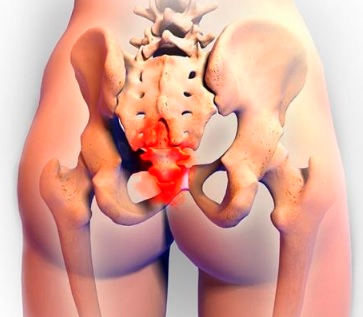

ბუასილის სტადიები

მე ქსელში ვნახე ფოტო, რომელიც გავდა იმას რაც მე მქონდა. მარცხნივ ბუასილის მესამე სტადიაა (რომელიც მე მქონდა), მარკვნივ ჯანმრთელი სფინქტერი.